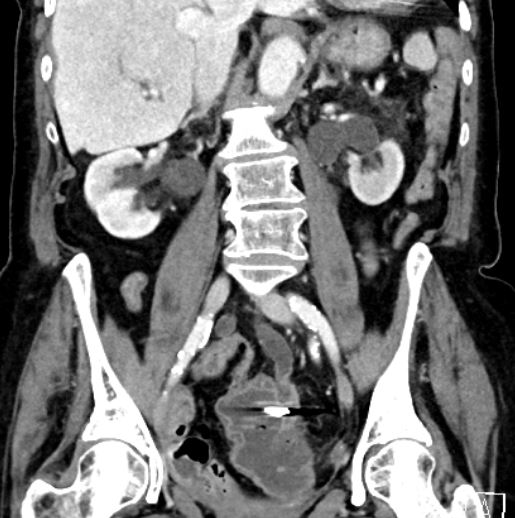

Ergebnisse: In der Akutdiagnostik zeigte sich sonographisch eine Harntransportstörung III° bds., laborchemisch ein akutes Nierenversagen mit einem Kreatinin von 2,3 mg/dl sowie eine beginnende Infektkonstellation (Leukozyten von 12,95 Tsd/µl, CRP von 3,7 mg/dl). Das im Anschluss durchgeführte CT zeigte eine Hydronephrose beidseits sowie ektatische Ureteren bis zur Insertionsstelle im Sigma, wobei die Clips in unmittelbarer Nachbarschaft lokalisiert schienen. Es erfolgte die Anlage von Nierenfistel-Kathetern (NFK) bds. sowie die koloskopische Entfernung der Clips. Laborchemisch normalisierten sich die Retentionsparameter. Nach 3 Wochen objektivierte eine antegrade Darstellung über die NFKs rechts einen regelrechten Abfluss, während sich links ein Kontrastmittelabbruch im Bereich der Einmündung des Ureters in das Sigma zeigte. Somit verblieb der NFK links als Dauerversorgung. Aufgrund des Patientenalters entschieden wir uns gegen eine Neueinpflanzung oder anderweitige Harnableitung.

Abbildung 3 [Abb. 3]